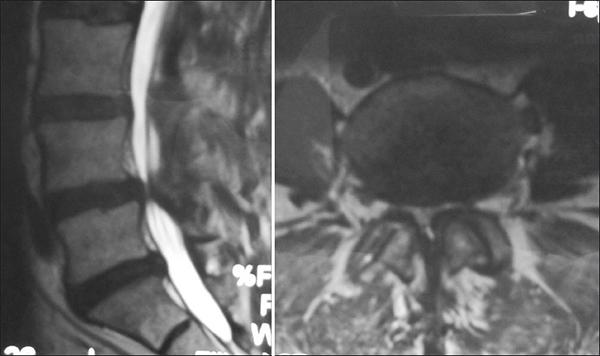

Figures A and B are the sagittal and axial CT cuts that show a T9 burst fracture with rotational malalignment and moderate retrolisthesis.